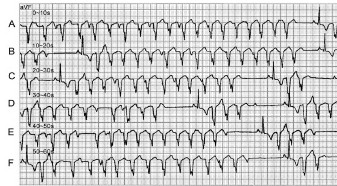

“不治之症”危及患儿 男性患儿,6岁时因心悸、气短在当地省级儿童医院就诊,被诊断为“病毒性心肌炎、扩张性心肌病(扩心病)、心力衰竭(心衰)合并窦性心动过速(窦速)”。患儿服用包括美托洛尔、利尿剂等在内的控制心衰及窦速的药物后,病情相对稳定。 3年后,患儿临床症状进行性加重,转至另一省级医院就诊,仍被诊断为“扩心病伴窦速”,给予相应治疗后疗效甚微。病情的逐渐进展导致患儿行动困难并长期辍学,同时家属也在“患儿病情严重,预后极差,可能需要心脏移植”的医嘱中惴惴不安。 2007年4月,患儿至我院就诊,当时查体心率为140次/分,血压为90/60 mmHg,双肺布满湿罗音,心前区明显隆起。X线胸片示心界明显扩大、心胸比例为0.70(图1)。超声心动图提示:左室明显扩大,左室内径65.3 mm,心肌运动呈弥漫性减弱,左室射血分数(LVEF)31%。上述证据均表明,患儿病情严重,处于心衰晚期。 “孰因孰果”困扰医师 对于经两家省级医院治疗6年,病情无法得以控制的患儿,明确其疾病诊断成为患儿入院后的当务之急。究竟是扩心病伴重度心衰及心动过速,还是心动过速引发了心律失常性心肌病,心衰与心动过速孰因孰果的疑问困扰着医师。 不同的诊断思路决定着不同的治疗策略。若以心衰为因、心动过速为果,难以解释患儿对心衰药物治疗无反应的事实。因此,以心律失常为因、心衰为果,由于患儿心动过速长期控制不佳而使心衰无法缓解的思路逐渐成为主流思路。 “对症治疗”孕育转机 随后的心内电生理检查证实,患儿存在房间隔附近的房速,经详细标测、反复诱发及确认后,其房速被成功消融。 1个月后,患儿病情明显好转,房速终止且心功能有所改善。1年后的随访结果显示,患儿心脏逐渐缩小,甚至完全恢复了正常(图2),心功能也随之改善,左室内径由65.3 mm缩小为46 mm,LVEF由31%升至66%。启示 患儿既往诊断为“心肌病合并心衰及心动过速”,几乎被认为是“不治之症”,而更正诊断为“房性心动过速诱发心肌病及心衰”后,由于射频消融可以根治房速,彻底去除病因,心衰自然可得以控制,这就是该患儿从“不治之症”到“重获新生”的关键所在。由上述典型病例可见,心律失常性心肌病的诊断至关重要,临床实践中亟待重视此类疾病,唯有正确诊断才能进行有效的对症治疗,勿让此类疾病再次成为“不治之症”。

图1 患儿术前X线胸片

图2 患儿术后1年X线胸片